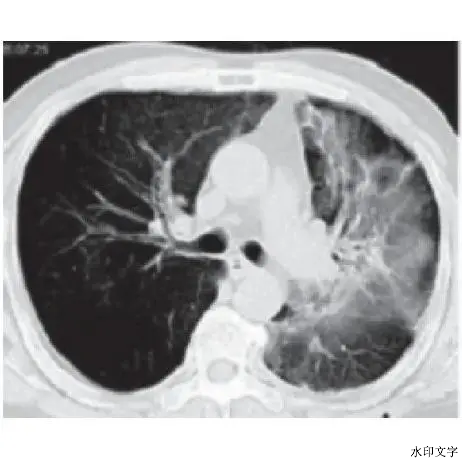

4.放射性肺炎

这是肺癌放疗中较严重的不良反应,但随着目前适形放疗的开展,放射性肺炎的发生率较以前减少。

一旦发生放射性肺炎,患者应暂停放疗,卧床休息,根据医嘱使用大剂量激素及抗生素直至好转。